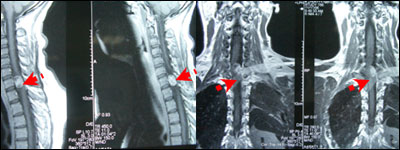

女性,30岁,胸背部疼痛2月半。入院查体:左侧霍夫曼征阳性,余无阳性体征。

术前图片: